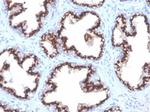

Prostein (p501S)/Solute Carrier Family 45 Member 3 (SLC45A3) Antibody in Immunohistochemistry (Paraffin) (IHC (P))

Prostein (p501S)/Solute Carrier Family 45 Member 3 (SLC45A3) Antibody (85414-RBM1-P1ABX) in IHC (P)

Formalin-fixed, paraffin-embedded human prostate carcinoma stained with Protein (p501S) Recombinant Rabbit Monoclonal Antibody (ZR9). HIER: Tris/EDTA, pH9.0, 45 min. 2 °: HRP-polymer, 30 min. DAB, 5 min. {{ $ctrl.currentElement.advancedVerification.fullName }} 验证信息 View more